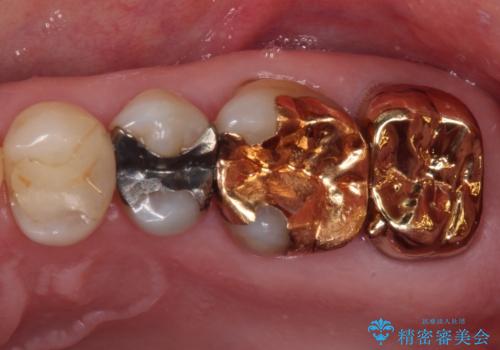

- 奥歯のクラウンが外れてしまったとのことで来院された患者様です。

土台の歯は、咬み合う下顎の歯と距離が近く、外れてしまったクラウンは、おそらく穴が空いてしまったのではないかと思われました。

距離が近いこと以外、特に大きな問題は認められなかったため、ゴールドクラウン(PGAクラウン)にて補綴することとしました。